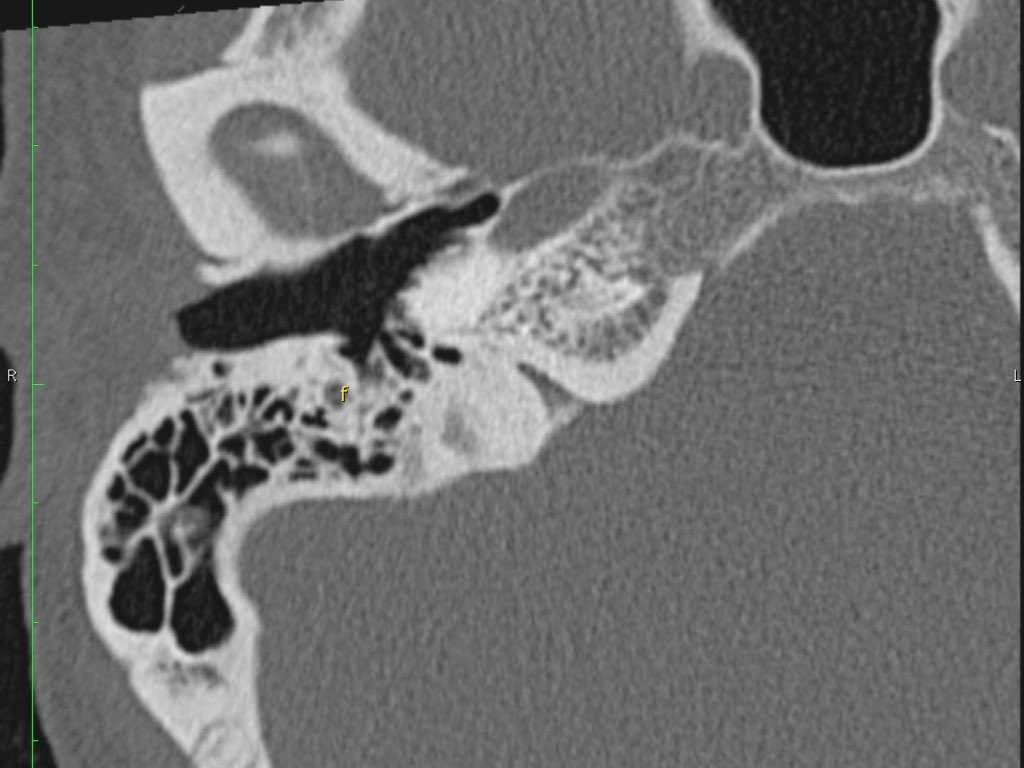

Trong bài tổng quan này, chúng tôi trình bày giải phẫu bình thường trên mặt phẳng cắt ngang (axial) và mặt phẳng cắt đứng ngang (coronal) của xương thái dương thông qua việc duyệt qua các hình ảnh.

Giải phẫu xương đá trên mặt phẳng cắt ngang (Axial)

Nhấp vào hình ảnh để phóng to.

Cuộn qua các hình ảnh.